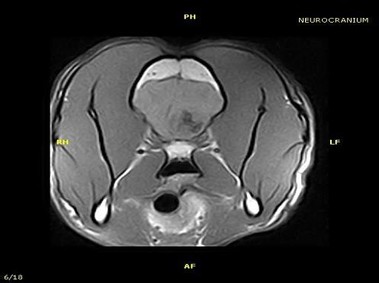

В настоящее время МРТ является наиболее предпочтительным методом визуализации любых мягких тканей, особенно для визуализации травм и патологий центральной нервной системы и суставов. Особенности Vet-MR позволяют использовать данный метод визуализации также в сфере ветеринарии.

Vet-MR специально разработана для визуализации небольших животных и является результатом внимания к деталям при разработке магнита, катушки и электронных компонентов, обеспечивая высокое качество экономически эффективной и простой в использовании МРТ в сфере ветеринарии.